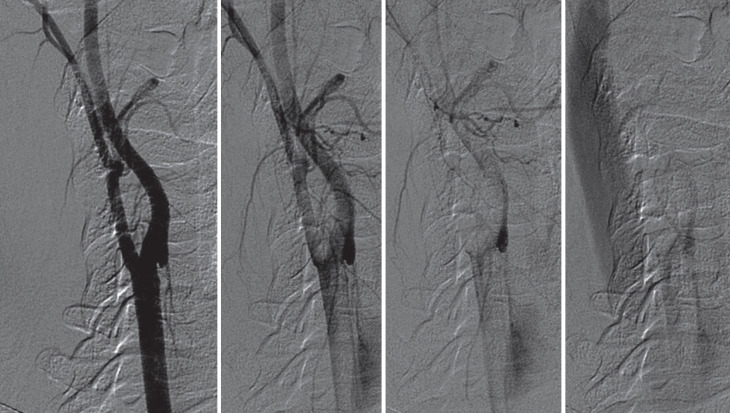

颈动脉网在50多年前被描述为非典型纤维肌肉发育不良(FMD)亚型,并有高度支持的病理证据作为内膜FMD。在接下来的几十年里,从导管血管造影或数字减影血管造影(DSA)到无创成像技术的转变以及病理程序的急剧减少导致了这些信息的逐渐丢失。目前,由于颈动脉网与隐源性缺血性脑卒中的关系,人们对其的关注有所增加。事实上,潜在的假设是颈动脉网的形态特征可能决定了动脉对动脉栓塞的血栓形成潜力。颈动脉网的病理允许识别嵌入在网袋中的小血栓,并且从颅内动脉血管内取出的血栓的特征非常相似。颈动脉网的诊断通常采用非侵入性技术,如计算机断层血管造影、超声和磁共振成像,需要两种不同技术的一致性来确认诊断。在诊断不确定的情况下,当考虑介入治疗缺血性中风或颈动脉网时,通常考虑DSA。有症状病例的治疗选择包括药物治疗(单或双抗血小板)或介入治疗(手术或支架置入术),但没有关于治疗的随机对照试验。本综述的主要目的是介绍目前关于颈动脉网的知识,检索FMD的历史数据和血管造影分类,并讨论在症状病例中与卒中相关的生物学合理性,以及更新FMD分类的必要性,以及前瞻性数据。

Carotid web was described more than 50 years ago as an atypical fibromuscular dysplasia (FMD) subtype with highly supporting pathological evidence as intimal FMD. In the following decades, the transition from catheter angiography or digital subtraction angiography (DSA) to non-invasive imaging techniques and the dramatic decrease in pathological procedures contributed to the gradual loss of this information. Currently, attention on the carotid web has increased due to its association with cryptogenic ischemic stroke. In fact, the underlying hypothesis is that the morphological features of the carotid web may determine a thrombogenic potential with artery-to-artery embolism. The pathology of the carotid web allowed identification of small thrombi embedded in the web pouch, and the features of thrombi endovascularly retrieved from intracranial arteries are very similar. The diagnosis of carotid web is usually made by non-invasive techniques, such as computed tomography angiography, ultrasound, and magnetic resonance imaging, requiring the concordance of two different techniques for confirming the diagnosis. DSA is usually considered in cases of diagnostic uncertainty and when interventional treatment of ischemic stroke or carotid web is considered. Treatment options in symptomatic cases include medical therapy (single or dual antiplatelets) or interventional approach (surgery or stenting), but there are no randomized controlled trials about therapy. The main aim of this review is to present the current knowledge on carotid web, retrieving historical data and angiographic classifications of FMD, as well as to discuss the biological plausibility of the association with stroke in symptomatic cases and the need for an updated classification of FMD, together with prospective data.